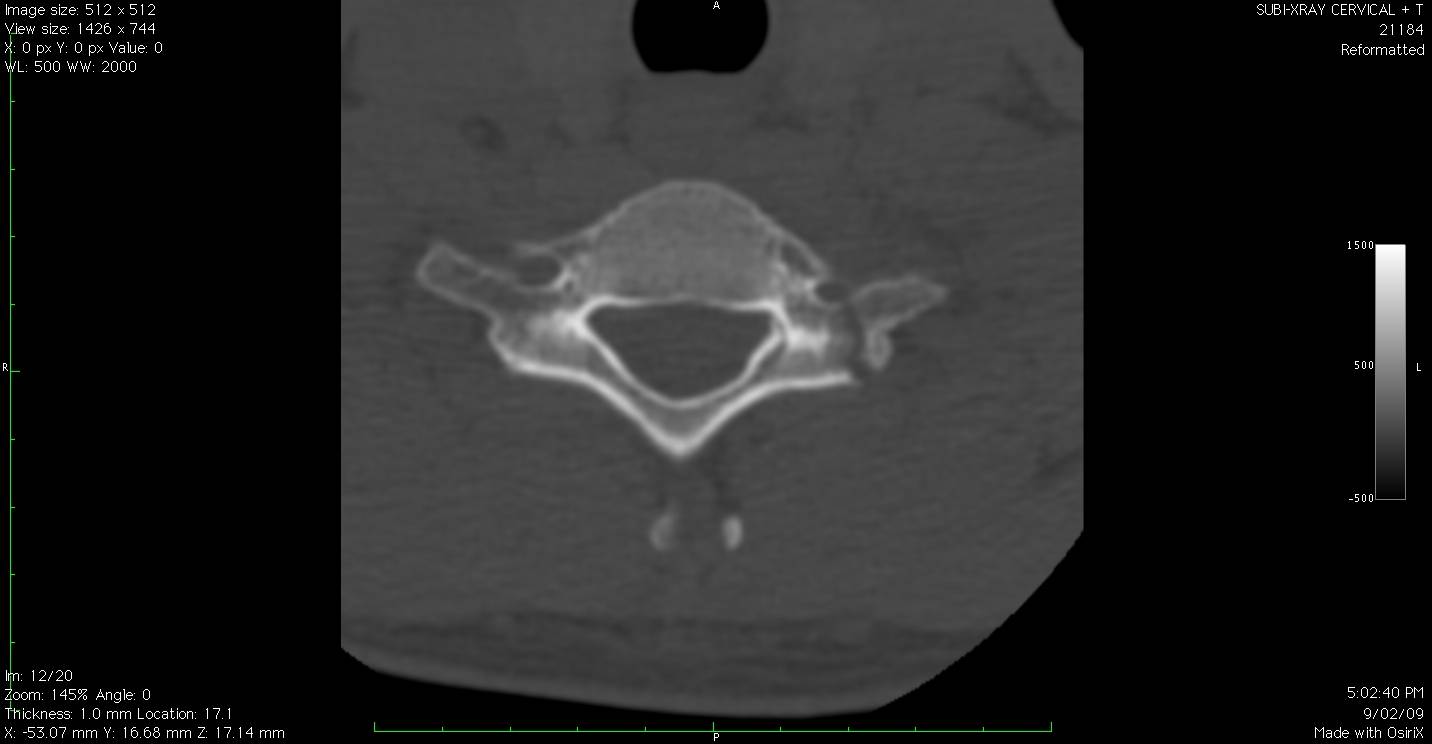

Broken chunk on the right hand side of the image

In my neck... :)